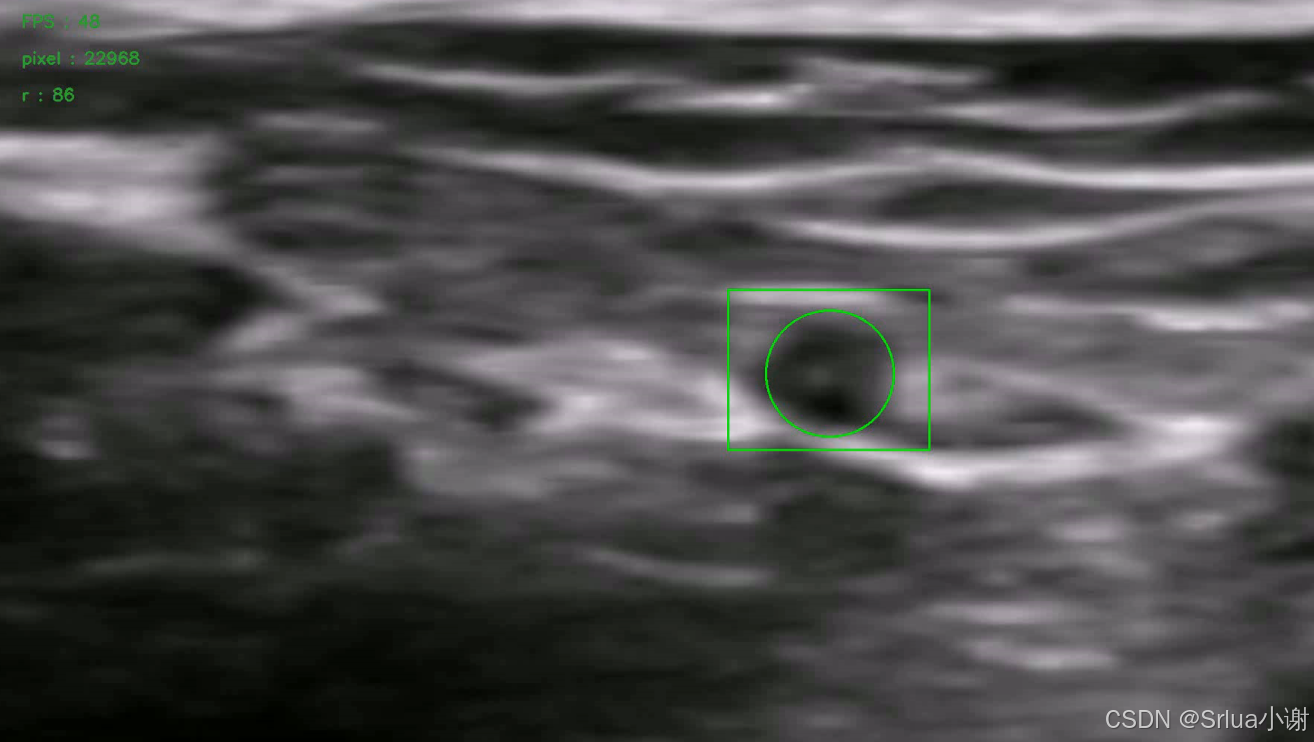

检测效果如图苏所示。

该算法可以实时计算血管的半径以及收缩状况,我们并将圆心和半径组成的圆实时可视化显示,效果图如所示:

具体的演示效果可以参考演示视频。